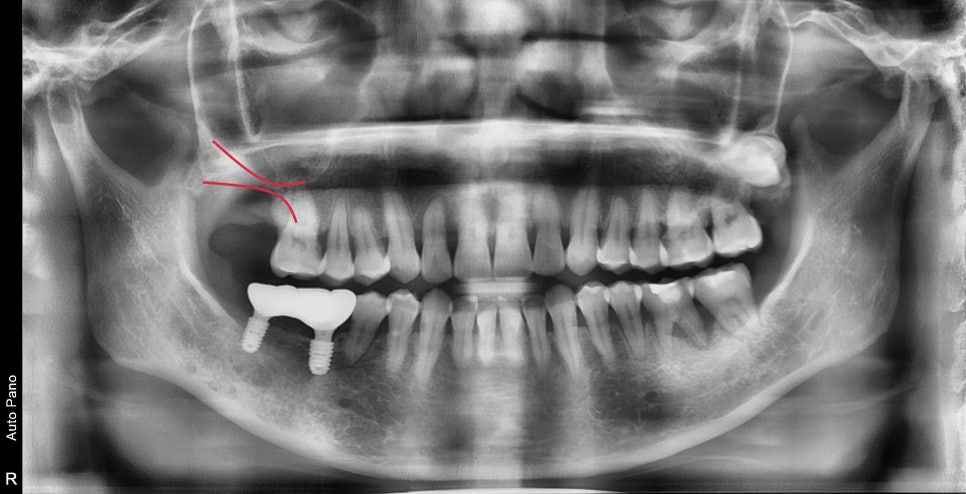

발치 후 3개월 정도의 시간이 지나서 주변골의 리모델링이 완료된 후의 사진입니다.

예상했던 대로 최후방 치아의 뿌리의 절반이 뼈로 덮여있어야 할 부분이 재생되지 않고 그대로 노출되어 있었습니다.

이런 경우 시간이 지날수록 노출된 뿌리의 시린 증상이 전과 똑같아질 것이고

임플란트의 유지적인 측면에서도 동시에 수술을 해서 고정력을 확보하는 것이 더 중요했습니다.

(표시된 선의 잔여골이 매우 부족하기 때문에 상악동 거상술이라는 뼈이식과 동시에 맨 끝 한 개의 임플란트만 수술을 한다면

임플란트 고정력이 상당히 낮아질 것입니다.)